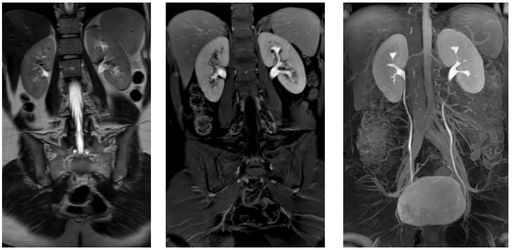

Voies urinaires, prostate, testicules

ANNET L. - UCL

Urinaire

MASTER 1

Testicule